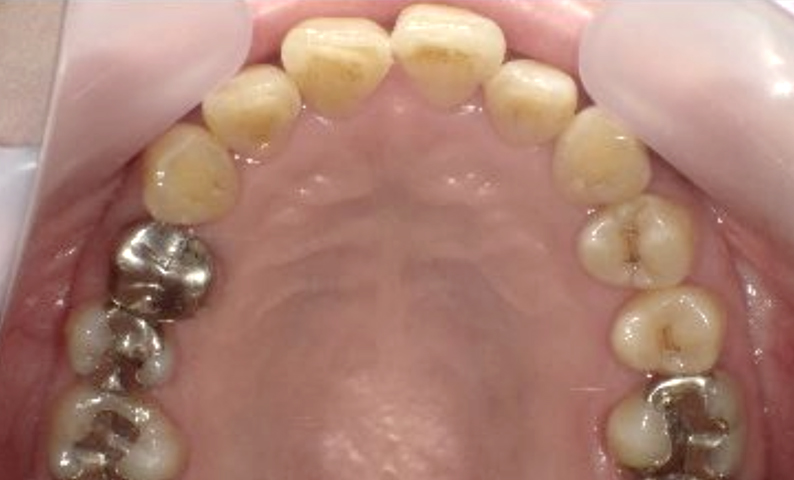

症例_003 下顎だけの部分矯正

治療期間:10ヶ月金額:24万円+税女性前歯のガタガタ下の前歯だけ上顎は補綴治療中

| Before | After |